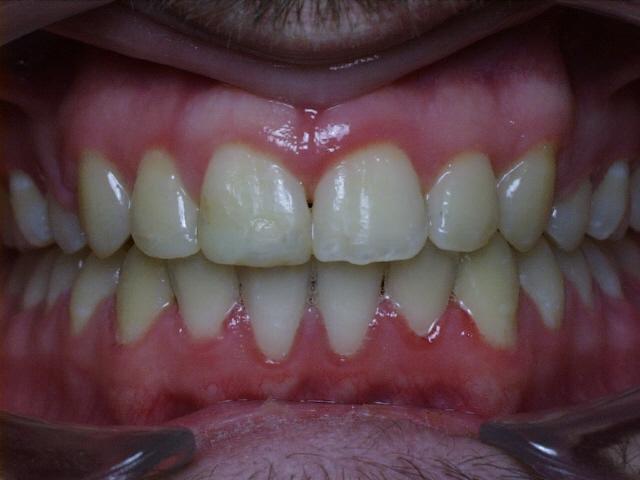

Moderate crowding with crossbites of the front teeth.  Treatment time was 24 months.  No permanent teeth were extracted in this case, but two deciduous cuspids seen in the initial photo were extracted after the braces were placed.  The molars were class 3 (lower molars too far forward at the start of treatment).